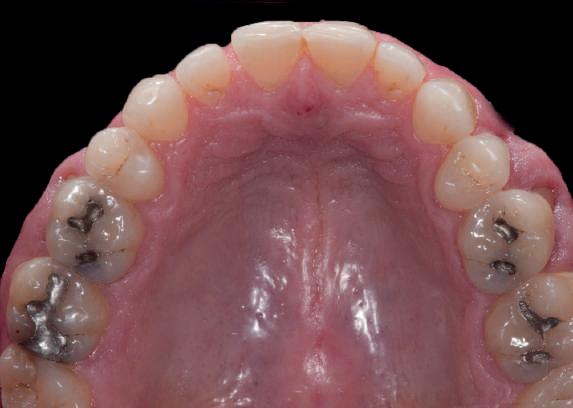

Acest pacient s-a prezentat cu o punte 1.3.-2.3. compromisă.

Pentru a păstra limitele restaurării fixe pe toată durata tratamentului, s-au inserat în primă etapă implanturi corespunzător 1.3. şi 2.3. După integrarea acestora, s-au aplicat bonturi individualizate, iar restaurarea provizorie s-a rebazat pentru suplimentarea suportului.

Implanturile şi bonturile ulterioare aferente s-au putut poziţiona în poziţiile 1.2. şi 2.1. Incisivul 1.1. a beneficiat de tratament endodontic electiv pentru a fi redus şi în cele din urmă, după inserarea bonturilor pe implanturile 1.2. şi 2.1., a fost scufundat (fig. 20, 21).

Atitudine: În fig. 21, este evident că, după submersiunea radiculară, nu se

obiectivează recesie în jurul bonturilor 1.2. şi 2.1. De notat osul excelent vestibular în dreptul tuturor implanturilor, fără recesie în jurul 1.3. şi 2.3. (fig. 22) care au fost inserate cu 8 luni înainte de 1.2. şi 2.1. Perioada scursă între scufundarea rădăcinii (fig. 20) şi inserarea punţii finale (fig. 22) a fost de 7 luni (fig. 23).

Figurile

20. Dintele 1.1. tratat endodontic.

21. Dintele 1.1. submersat în cele din urmă după inserarea bontului la nivel 1.2. şi 2.1.

22. Os excelent vestibular faţă de toate implanturile; nicio recesie la nivelul 1.3. şi 2.3. 23. Punte provizorie pe toate bonturile.